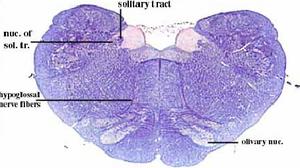

correspondencias entre la localización de los núcleos neuronales en diferentes cortes.

esquema de los diferentes núcleos aferentes y eferentes